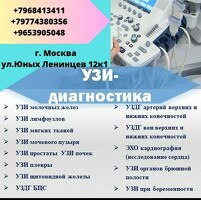

Косметология,терапия ,гинекология,узи ,анализы .

Косметлогия ,гинекология,терапия ,эндокринология,дерматология,репродуктолог,узи анализы

Медицинский центр возле метро Котельники. Предлагаем услуги : узи, гинекология ( аборт, фармаборты, лечение кровотечений, лечение БЕСПЛОДИЯ, удаление полипов), ХИРУРГИЯ( удаление геморроя, лечение анальных трещин, удаление паховых грыж) Урология( лечение инфекций, лечение простатита), КАРДИОЛОГИЯ( ЭХО, ЭКГ, ХОЛТЕР), СТ...